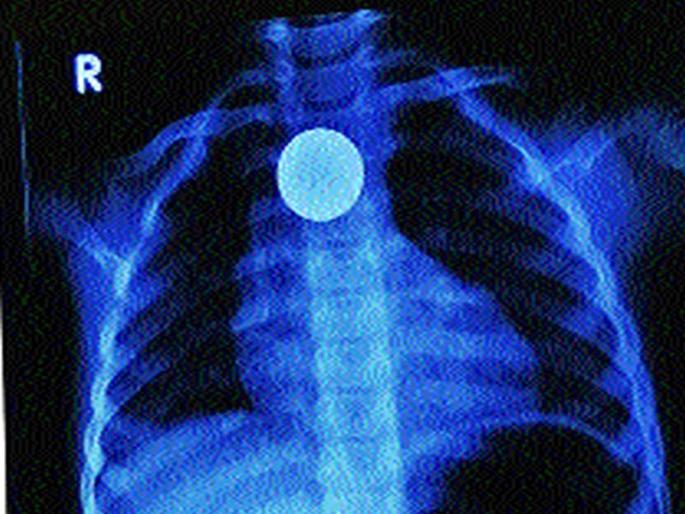

मुंबई : दहिसर येथील तीन वर्षांच्या चिमुरडीने घरात खेळताना पाच रुपयांचे नाणे गिळले. नाणे गिळल्यामुळे या चिमुरडीला श्वसनास त्रास उद्भवला, त्याचप्रमाणे बोलण्यास अडथळा निर्माण होत होता. परंतु, पालकांनी तत्काळ बोरीवली येतील खासगी रुग्णालयात तिला दाखल केले. तेथील डॉक्टरांनी एन्डोस्कोपीच्या साहाय्याने हे नाणे बाहेर काढले. आता त्या चिमुरडीची प्रकृती स्थिर असल्याची माहिती डॉक्टरांनी दिली आहे.

एन्डोस्कोपीसाठी गॅस्ट्रोएन्टेरॉलॉजी विभागाचे प्रमुख डॉ. राजीव हिंगोरानी यांच्या मार्गदर्शनाखाली त्यांच्या चमूने उपचार केले. आपत्कालीन एन्डोस्कोपी प्रक्रिया करून ते पाच रुपयांचे नाणे यशस्वीरीत्या बाहेर काढले. अन्ननलिकेवाटे नाणे बाहेर काढताना ते श्वास नलिकेत पडू नये याची विशेष खबरदारी डॉक्टरांना घ्यावी लागली.

पाच रुपयांचे नाणे गिळल्यामुळे चिमुरडीला श्वसनास त्रास उद्भवला होता, त्याचप्रमाणे बोलण्यास अडथळा निर्माण होत होता. हे नाणे डॉक्टरांनी आपत्कालीन एन्डोस्कोपी प्रक्रिया करून यशस्वीरीत्या बाहेर काढल्याने चिमुरडीचा जीव वाचला आहे.